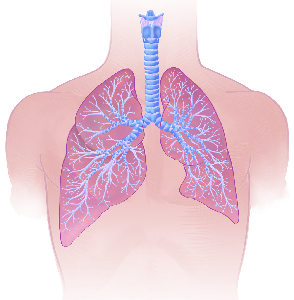

Detailreiche Fotografien aus der medizinischen Praxis ergänzen die Texte; moderne, genaue,

wissenschaftliche Zeichnungen geben Einblick in die Anatomie und die Funktion der Lunge und

anderer Organe.